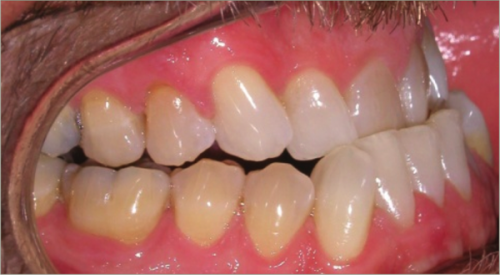

42 year old male:

Diagnosis:

- Skeletal underbite

- Retruded upper jaw, protruded lower jaw

- Full arch crossbite

- Lower arch crowding